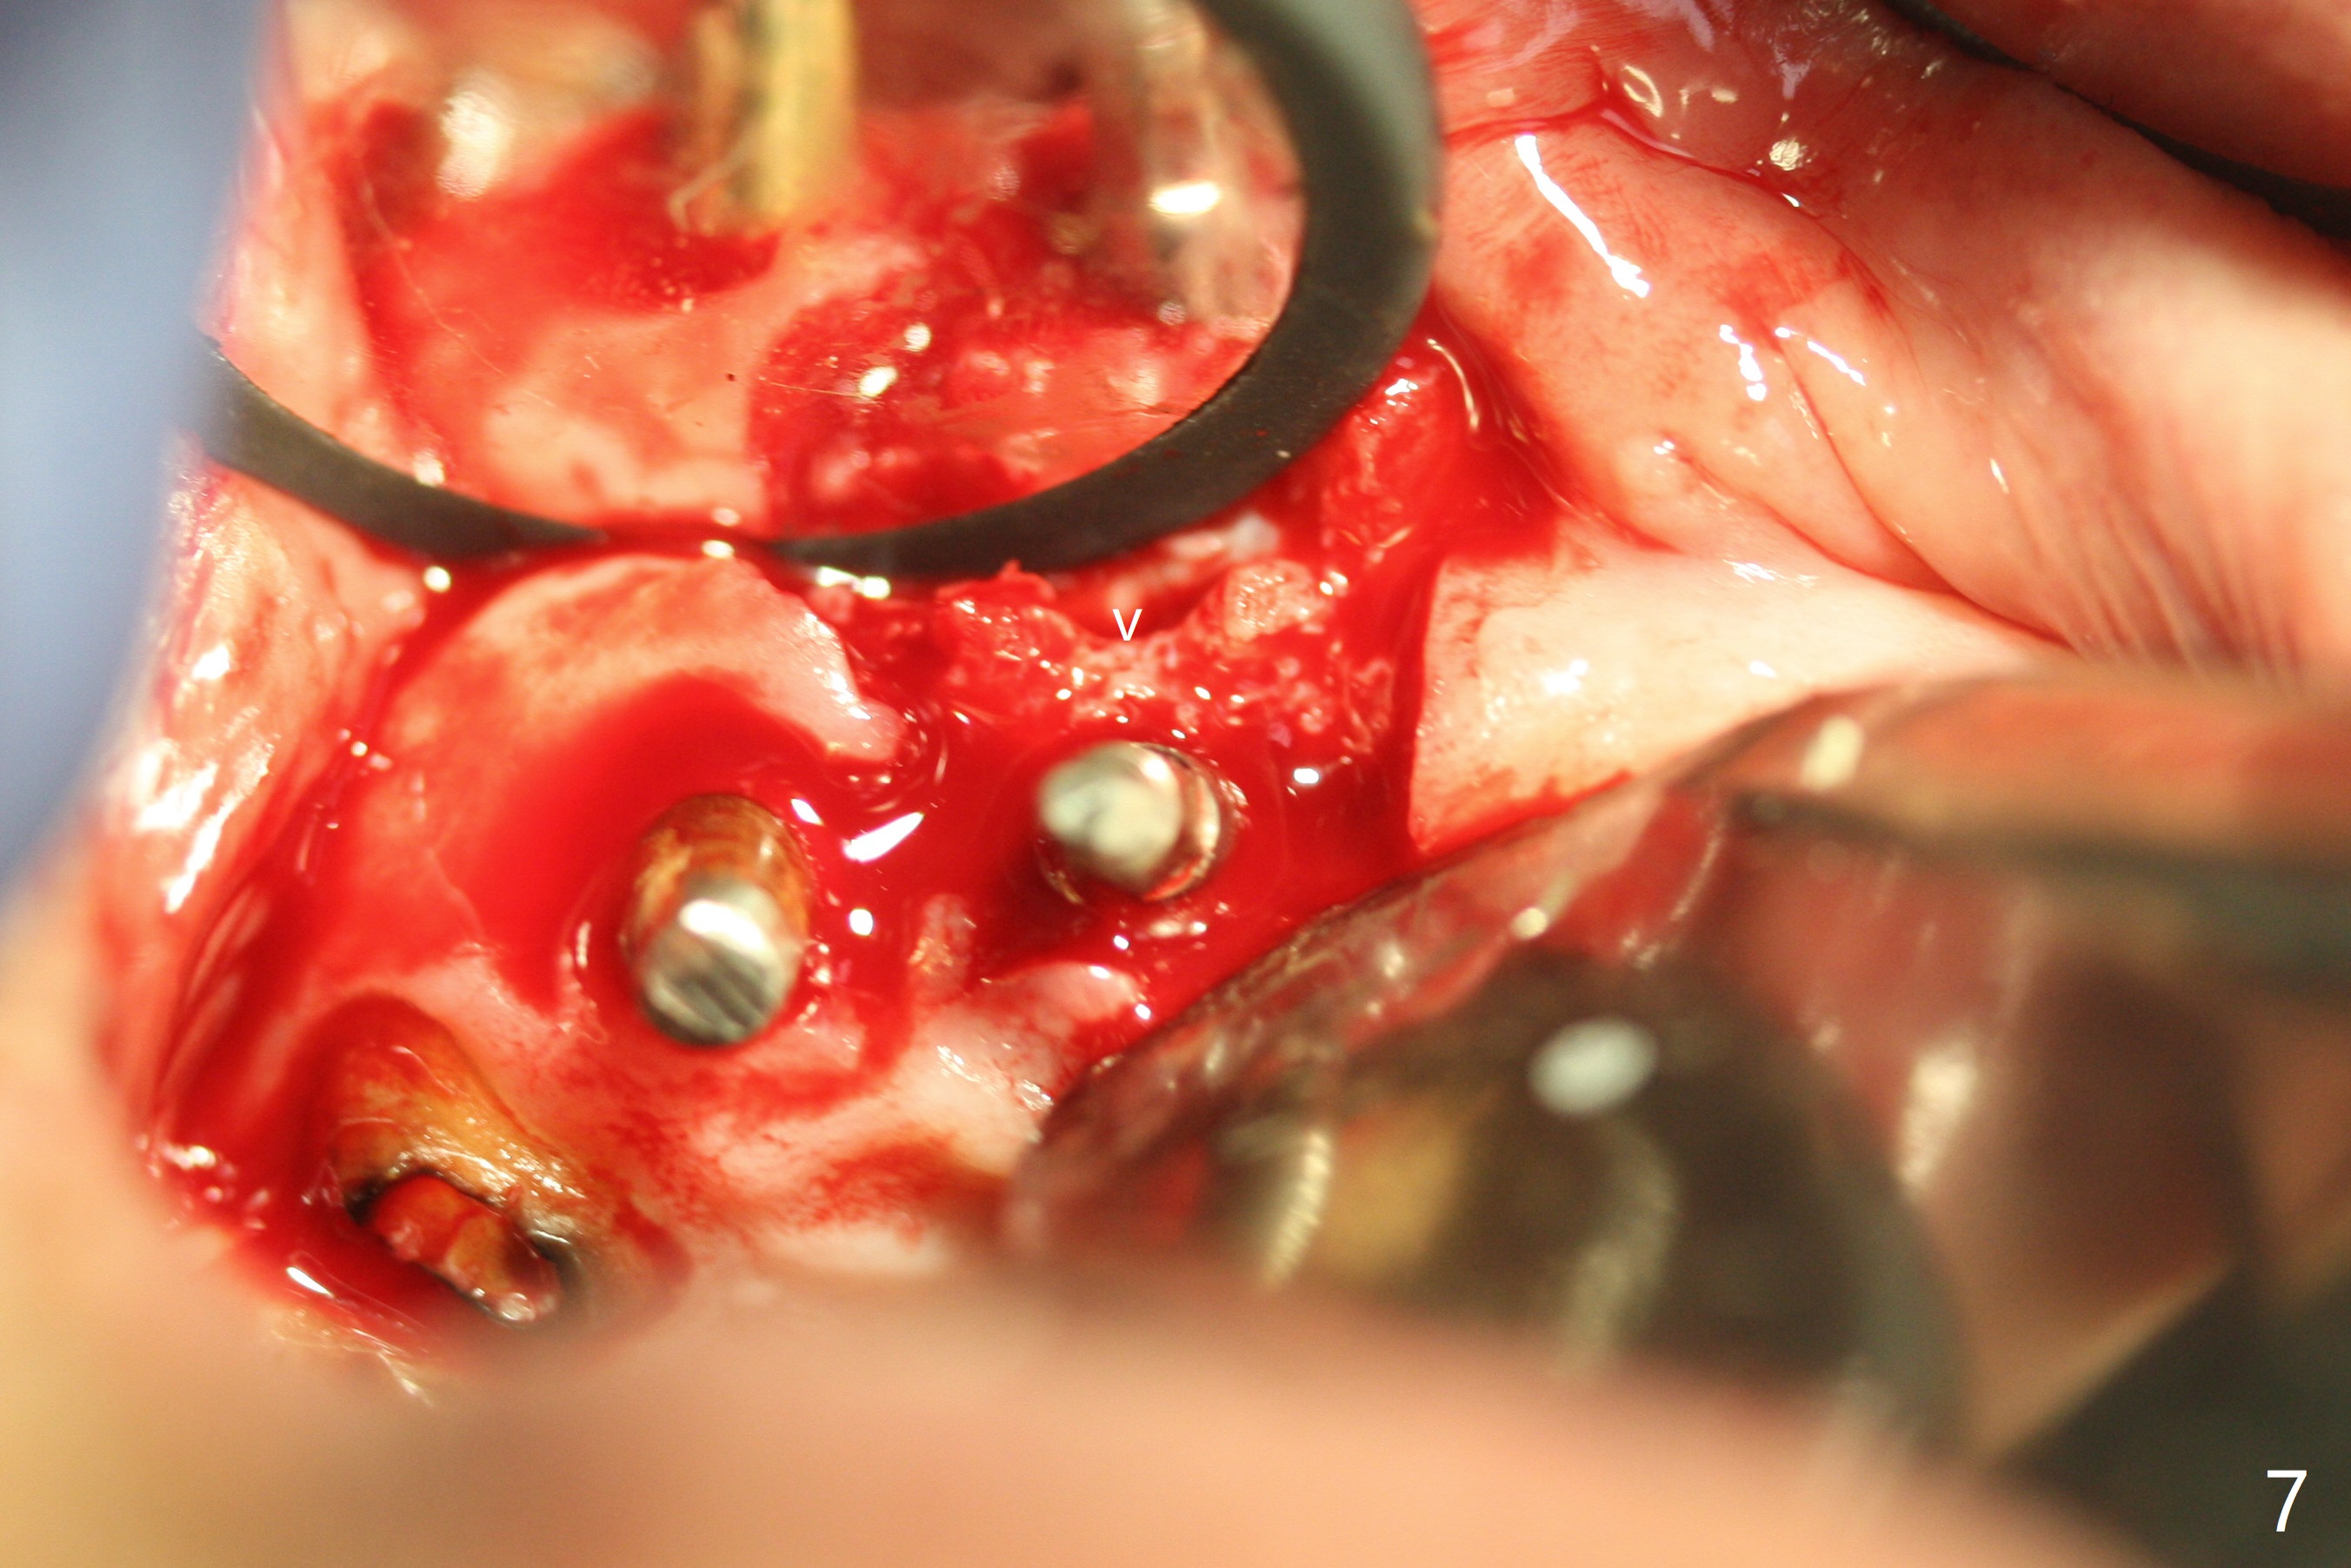

To have enough clearance for the splinted provisional at #6-12 (Fig.1 *), composite has been placed in the posterior teeth (bilateral, *, Fig.2). When the composite is removed, there is no clearance between the implants/abutments of #7 or 10 (Fig.3). Incision is made with removal of the 1-piece implant at #7; there is enough bone to move the osteotomy buccal (Fig.4 arrowhead). When the same implant is placed buccal (Fig.5), there is sufficient clearance for restoration (Fig.6 *), while there is still enough buccal bone left (Fig.7). When the patient returns 5.5 (for #7 and 10)/6.5 (#6,11,12) months postop, his chief complaint is tenderness lingual to #11. In fact, the abutment screw is loose at #11, while the implant at #10 has mobility (Fig.8), which is related to loss of the posterior stops (*) due to wear. There is slight bone loss mesial to #10 implant 5.5 months postop (Fig.10, as compared Fig.9). CBCT taken 5.5/6.5 months postop shows no bone loss (Fig.11-15). The 3x14 mm 1-piece implant at #10 is mobile 9 months postop and is removed and replaced by a 3.5x13 mm 2-piece one with slightly buccal osteotomy (Fig.16). PAs are taken prior to impression (Fig.17,18). The abutment at #12 is loose (<). More composite needs to be added to the occlusal surface of the upper posterior teeth. Finally the patient agrees to have crowns for the upper posterior teeth.